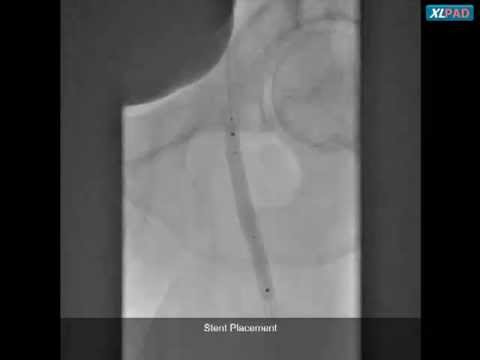

Viance, Subintimal Re-entry, and Stenting for Mid SFA CTO